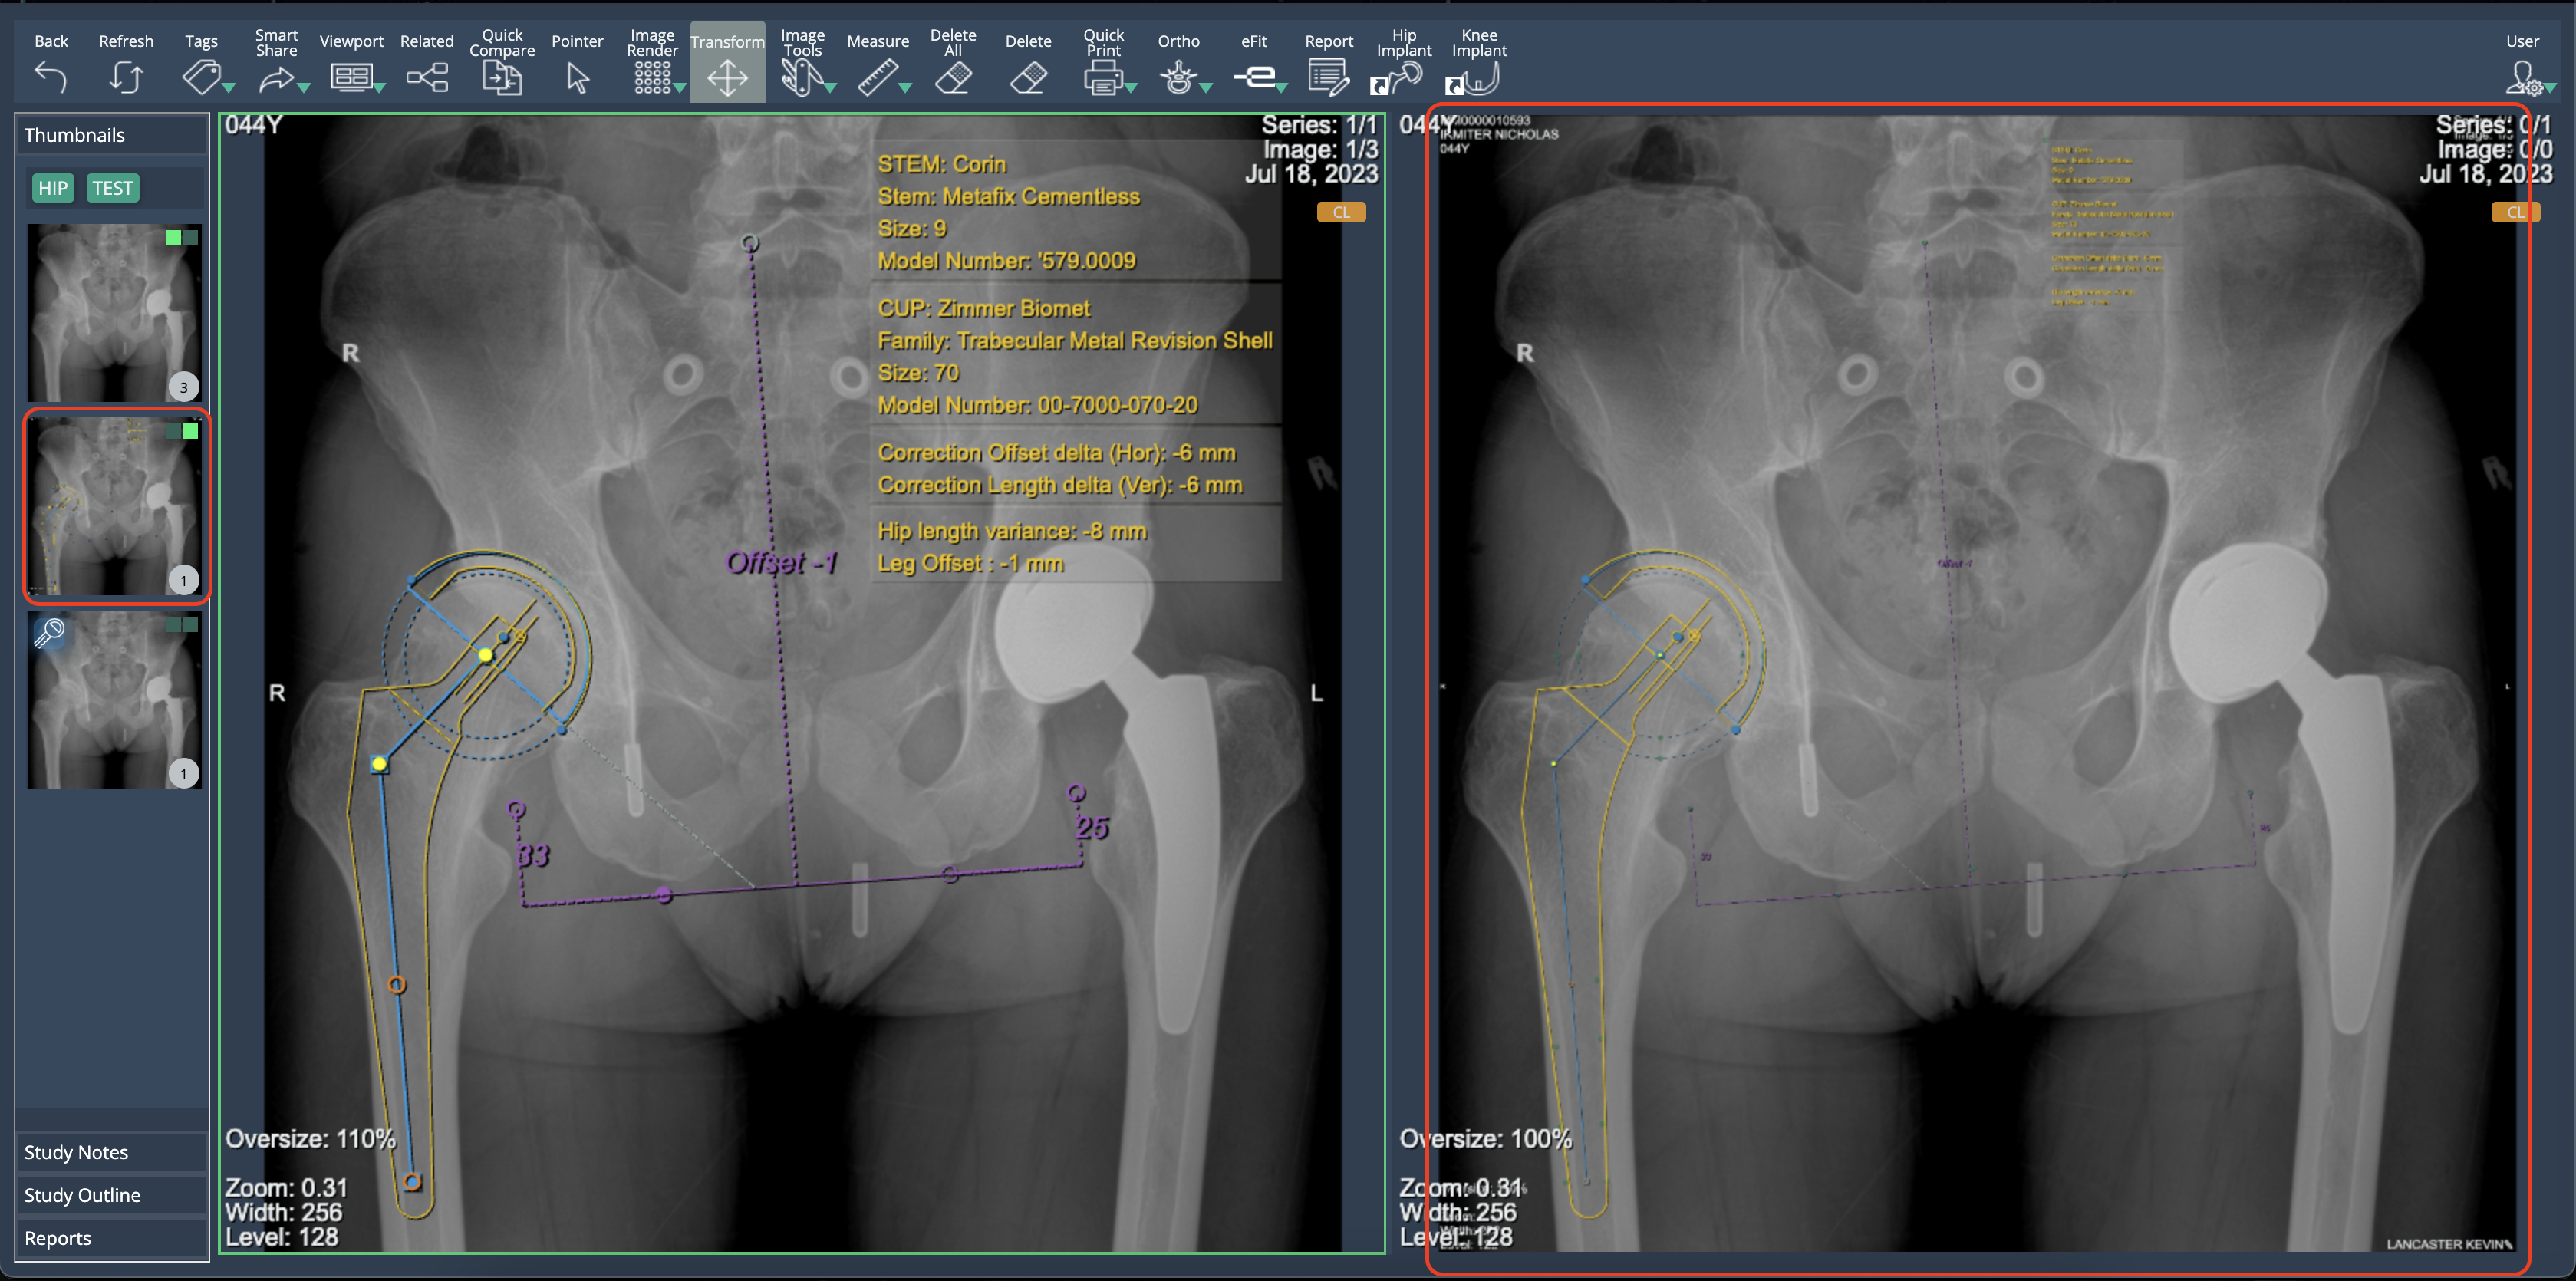

New DICOM image generation in eFit

eFit now creates a new DICOM image in a separate series when saving a template. This image contains the implant planning information for hip and knee templates, ensuring compatibility with external DICOM viewers.

eFit now provides visibility of implant model information. When templating a hip or knee, the implant model number is displayed in the property list of each component. This information is available in the table shown when selecting "Show in Print", ensuring users have quick access to implant details.

Template Image Integration in eFit Reports